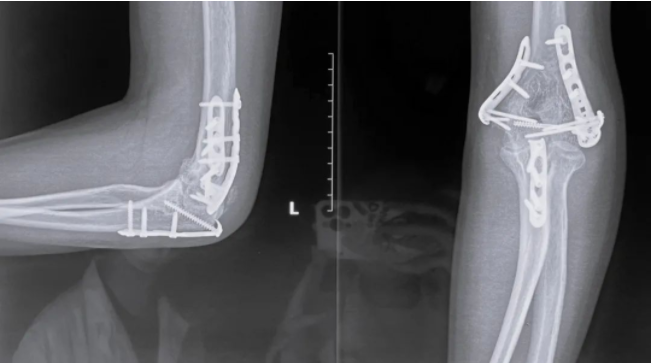

骨化需要松解的X光片